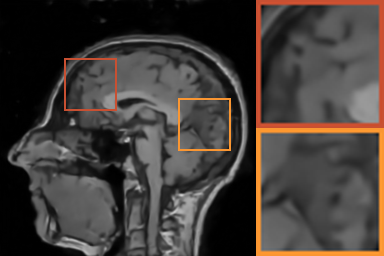

As shows in Fig. 1, at the first several iterations, the loss of is slightly larger than that of . Because the input is corrupted with severe artifacts, thus the role of data-driven module is significant at the first several steps. But as process goes on, repeated denoising operation in turn causes over-smoothing. While module can make up for it by incorporating model based knowledge. Though can improve the performance, it cannot ideally converge to a desired solution. The solid line indicates the superiority of Ours over other choices in both convergence rate and reconstruction accuracy. The execution time of , , and Ours is 4.4762s, 3.3240s, 6.2760s and 2.5225s, respectively. As expect, the proposed method provides a much faster reconstruction process. Thus we can verify that our framework has higher efficiency both in terms of theoretical convergence and practical execution time. The visualized results in Fig. 2 also verify that Ours has better performance than others.

First, we test on 25 T1-weighted MRI data using three different undersampling patterns with a fixed 10% sampling rate. Fig. 3 shows the quantitative results (PSNR). Our method performances best for all three cases and has stronger stability compared with the second best method on variance. As for the effect of sampling ratios variation, we use radial mask under 10%, 30% and 50% sampling rates with evaluation of RLNE and MSE. Fig. 4 shows that our method has the lowest reconstruction error for all sampling rates. For more intuitive comparison, we illustrate the reconstruction error in term of pixels in Fig. 5. We also offer the qualitative comparison in Fig. 6. Visualized results demonstrate our method has better performance in both artifacts removing and details restoration. Time consuming is also considered. We compare our method with others on the 25 T1-weighted data using Radial mask with 10% and 50% sampling rate. Notice that ADMM-Net and ours are tested on GPU for the incorporation of deep architecture. Tab. 1 shows that our method provides an efficient reconstruction process and comes to the fastest method among the state-of-the-art competitors.

To demonstrate the robustness of our approach, we first apply it on various MRI data including the chest, cardiac and renal (?). In Tab. 2, Our proposed framework gives the highest PSNR for all of the tree types of MR images. Fig. 7 visualizes the corresponding results for chest data. we can see that our approach prevails over others in detail restoration at the junction of blood vessels as well as noise removal in the background. Actually, our method has a stronger ability to handle slight noise because of the subprocess of learning based optimization with deep prior. To demonstrate that, we add Rician noise at level of 20 to 25 T1-weighted MRI and 25 T2-weighted MRI to generate the noisy data. As what is shown in Fig. 8, our method over leads all the competitors by a large margin when the input is corrupted with Rician noise.